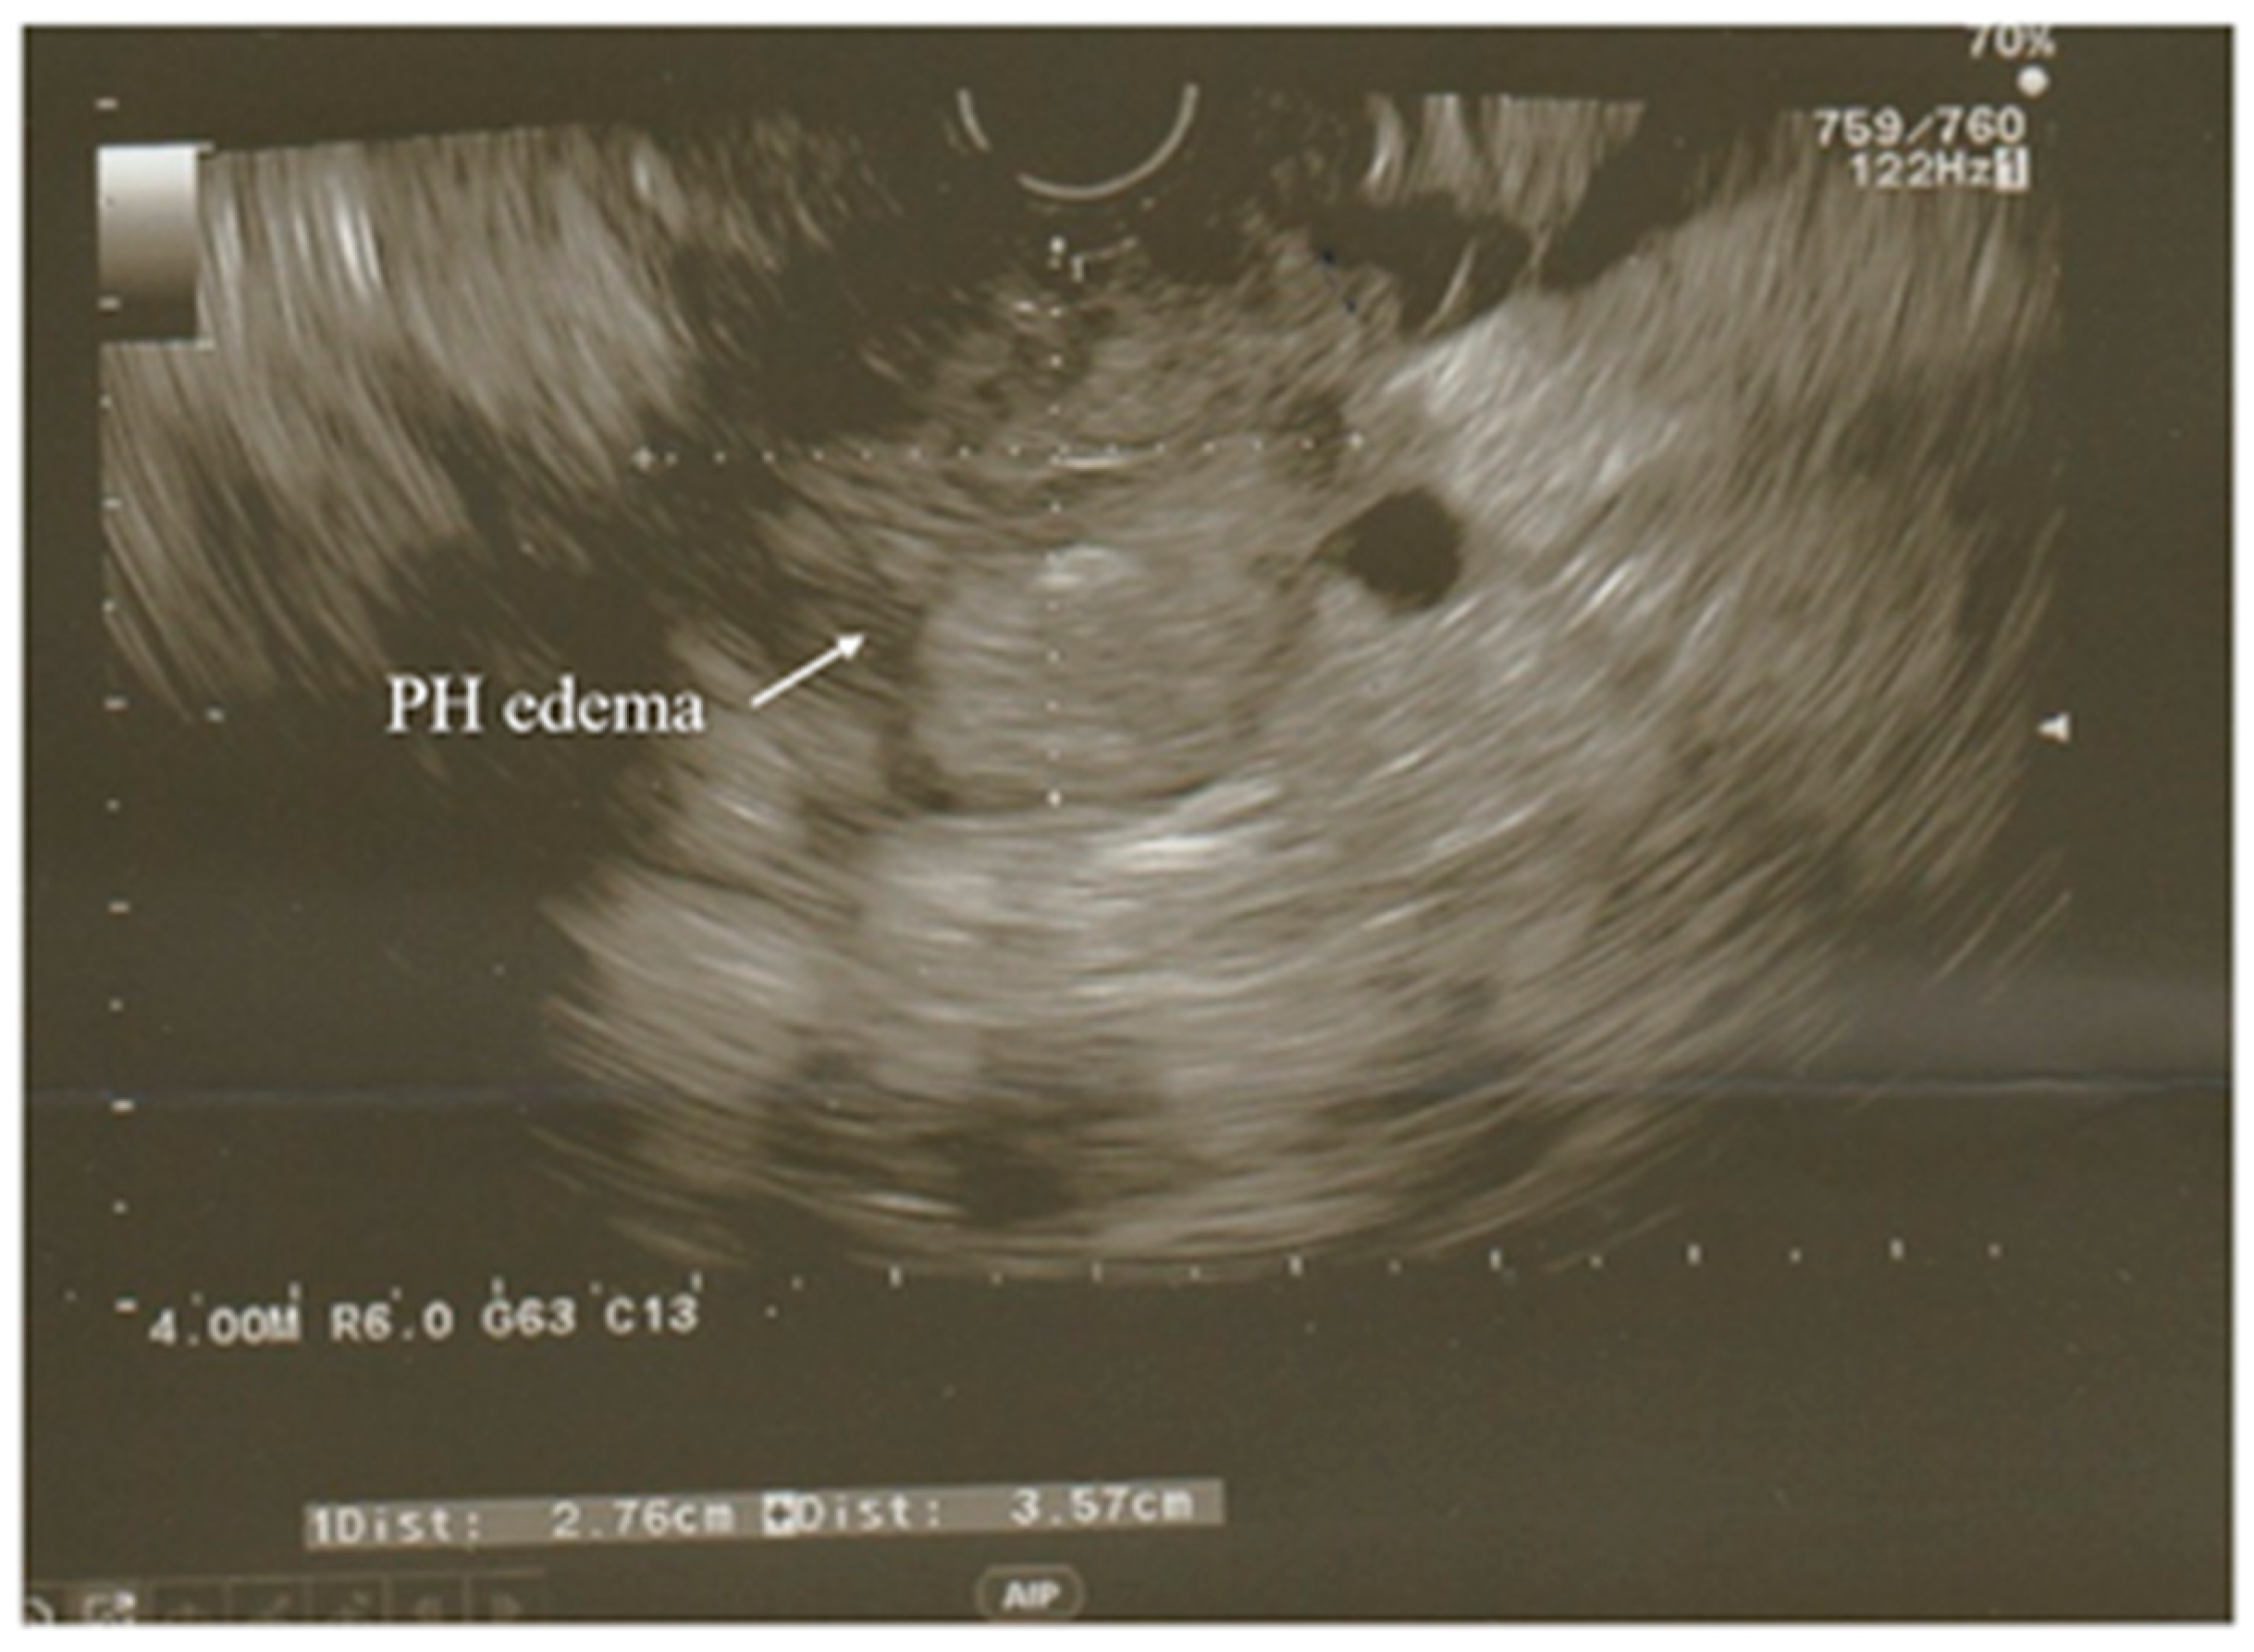

3.3. Ultrasonography

- Rizk, M.K.; Gerke, H. Utility of endoscopic ultrasound in pancreatitis: A review. World J. Gastroenterol. 2007, 13, 6321. [Google Scholar] [CrossRef]

- Kotwal, V.; Talukdar, R.; Levy, M.; Vege, S.S. Role of endoscopic ultrasound during hospitalization for acute pancreatitis. World J. Gastroenterol. 2010, 16, 4888. [Google Scholar] [CrossRef]